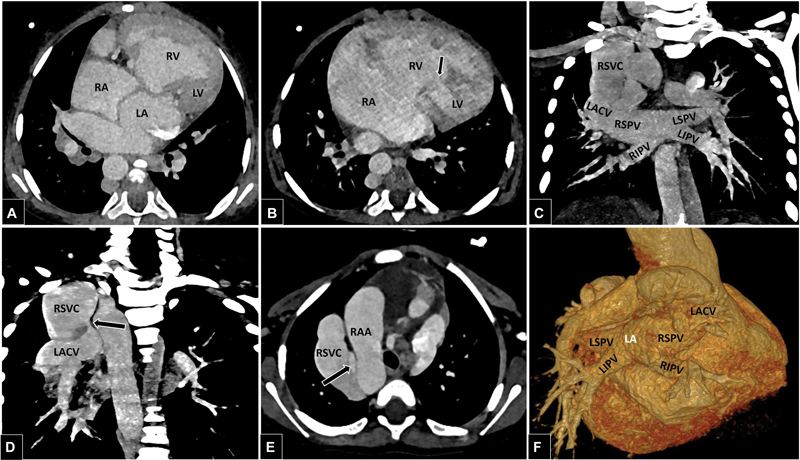

持续性左心静脉(LACV)是一种罕见的肺静脉异常,其特征是胚胎期肺脏与全身的通讯持续存在。它通常与左心梗阻性病变有关,如左心发育不全综合征和二尖瓣闭锁。上腔静脉(SVC)和下腔静脉(IVC)的完全重复是罕见的,这是由于基数静脉系统多步骤发育的畸变而发生的。文献中有双SVC和IVC共存的报道;然而,其发生与持续性左心房静脉至今未见报道。目前的病例描述了这些复杂的肺静脉和全身静脉异常的罕见共存:双SVC和IVC患儿的持续左房心静脉。胚胎发育和可能的畸变导致这些异常也详细。

Persistent levoatriocardinal vein (LACV) is a rare pulmonary venous anomaly characterized by persistence of embryonic pulmonary to systemic communication. It is commonly associated with obstructive lesions of the left heart, such as hypoplastic left heart syndrome and mitral atresia. Complete duplication of the superior vena cava (SVC) and inferior vena cava (IVC) is rare, and occurs due to aberrations in the multistep development of the cardinal venous system. Coexistence of double SVC and IVC has been reported in the literature; however, their occurrence with persistent levoatriocardinal vein is hitherto unreported. The current case describes a rare coexistence of these complex pulmonary and systemic venous anomalies: persistent levoatriocardinal vein in a child with double SVC and IVC. The embryological development and possible aberrations leading to these anomalies are also detailed.